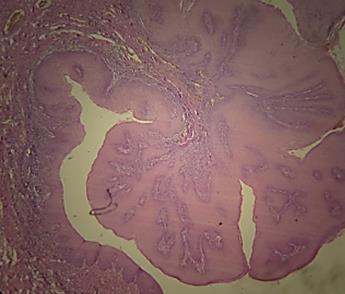

Presentación de caso clínico

Paciente masculino de 6 años de edadconíleometabólicodesdehace4años.

Inicia su padecimiento hace 1 año presentando una lesión en mucosa labial, la cualesexofítica,menora1cmdediámetro, asintomáticaydecrecimientolento.(Fig.3)

Se realiza biopsia excisional de la lesión. Donde se apreció presencia de coilocitos, numerosas proyecciones digitalizadas, crecimiento papilar y queratina engrosada. (Fig.4).Despuésdeentregareldiagnóstico de patología se recomendó seguimiento a largo plazo, porque puede recidivar dependiendo características del inmunológicasdelpaciente.

Fig. 4

Papiloma escamoso, autoría propia vista microscópica

Nota:Fototomadaporelautor